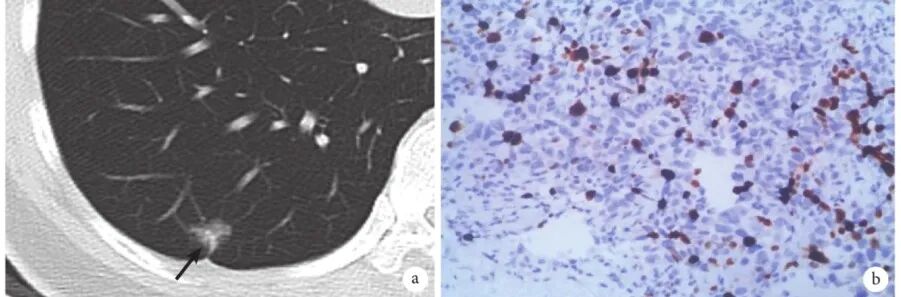

图5 CTR较低的混合磨玻璃结节肺癌患者影像学表现及病理

a:该结节(箭头)长1.0 cm×0.8 cm,有空泡征、分叶状、毛刺、血管集束征,CTR<25%,组织病理学证实为MIA,ⅠA1期;b:Ki-67表达3%(×200);CTR:实性成分比例;MIA:微浸润腺癌